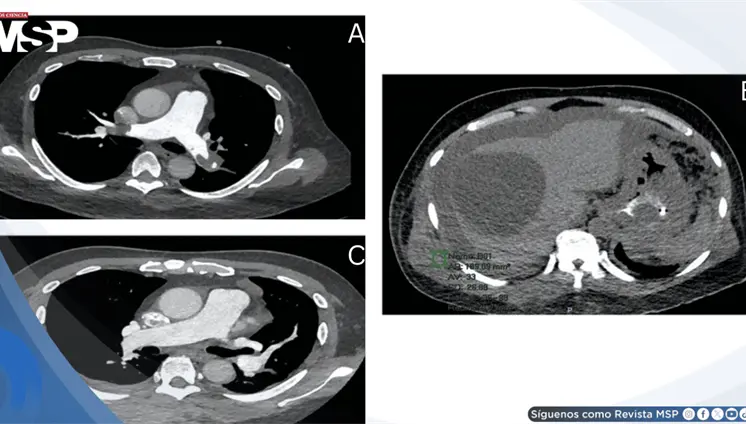

El estudio histológico confirmó un adenocarcinoma mucinoso de células en anillo de sello de vejiga con invasión muscular y diseminación metastásica pulmonar y ósea.